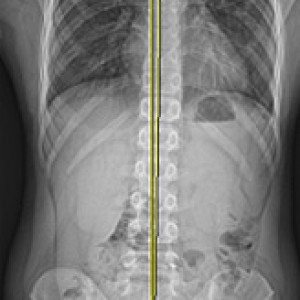

검사부터 다른 당당

“당당은 뼈만 보지 않습니다.”

근육과 근막의 정렬을 함께 진단하며, 풀 스파인 촬영을 통해 머리부터 모든 고관절, 발의 정렬까지 함께 파악하여 개개인에 맞는 전신 치료법을 설계합니다.

전신 엑스레이 검사

Before & After

해당 사진은 수정없는 실제 치료사진입니다.

환자의 치료결과는 환자의 상태, 치료방법 등에 따라 차이가 발생할 수 있습니다.